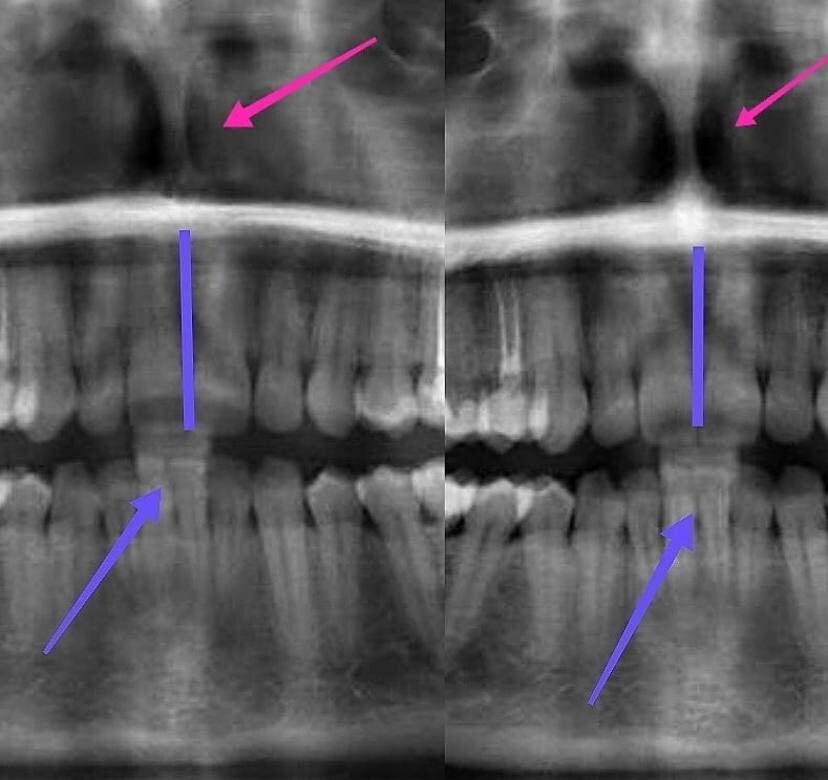

✔️ 3. Собственно перегородка. В карусели фото случая, когда перегородка действительно искривлена настолько, что блокирует половину носа и давит

на носовую раковину.

🎉 А теперь самое интересное: помимо постоянных откликов от моих курсантов об улучшении носового дыхания, у меня, наконец, появился снимок, где видно, что сама носовая перегородка от занятий стала ровнее, благодарю нашу девочку за предоставленное фото!)

Причем, смотрели на зубы (верхняя челюсть развернулась и встала на место центральная линия), а увидели еще и выравнившуюся перегородку!)

👇👇👇